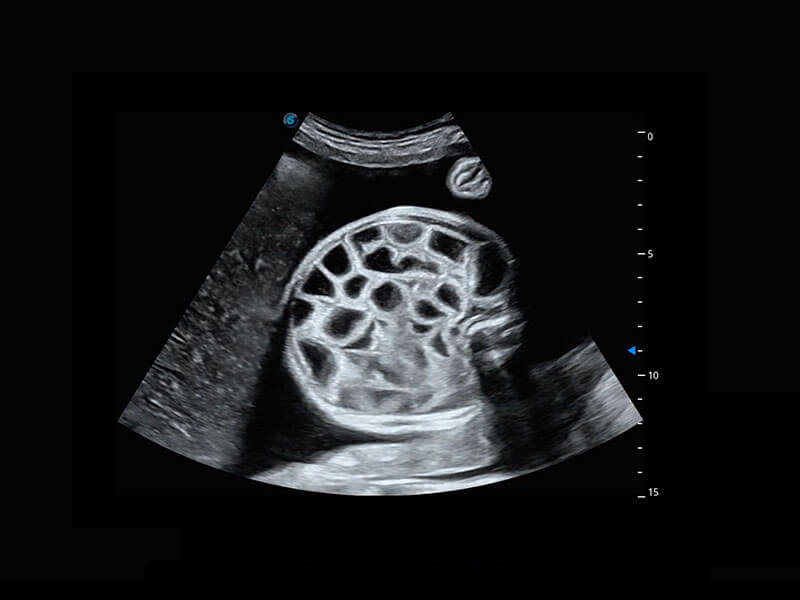

右室双出口

胎心容积成像